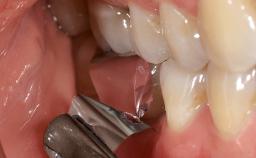

Surgical Management of Peri-Implantitis: Removal of Implant Due to Recurrent Infection Using an Implant-Retrieval Tool

Despite anti-infective surgical treatment, some patients may experience recurrent infection and progressive bone loss requiring additional treatment. This case describes a conservative approach using an implant retrieval tool without the need for excessive bone removal or use of a trephine.

A 65-year-old female patient was referred to the periodontist for assessment and management of infection associated with an implant at site 12. The general dentist had noted suppuration on probing during examination.